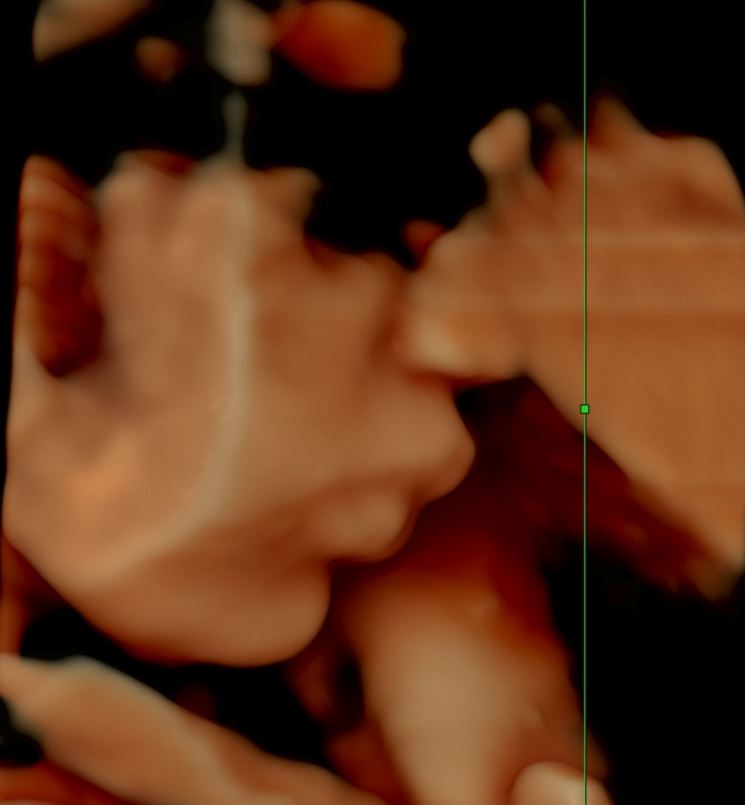

Pavlíček který už má dnes 2 měsíce a jeví se jako zdravé miminko měl NT hodnoty v 14 týdnu 9,5mm a celkový Hydrops.

NT hodnoty 5,4mm se během týdne zvedli na 9,5mm a Pavlík byl oteklý úplně celý.